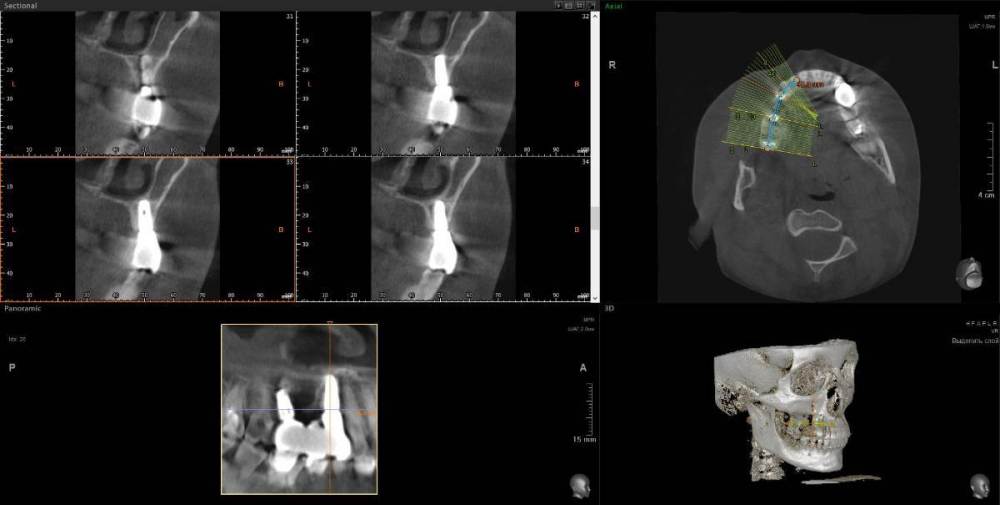

1. Сильное воспаление верхнего зуба привело к воспалению пазухи носа 2. Импланты 2 года (общая ст-ть 200 тыс.), тоже воспаление, рекомендовано удалить

1. Из-за сильного воспаления верхнего зуба костная кость растворилась и дошло до пазух носа. Зуб рекомендуют удалить

2. Импланты установила 2 года назад, в итоге заплачено было 200 тыс. с учетом циркониевых коронок. На КТ обнаружилось сильное воспаление, как следствие растворилась костная ткань импланты, доктор сказал уже не спасти.

Буду очень признательна за консультацию - действительно ли нужно удалять зуб и импланты? КТ во вложении

IMHO. Зуб 18 стоит удалить, зуб 17 стоит полечить. Имплантат в позиции 16, похоже, придётся удалить, имплантат в позиции 14, на мой взгляд, вне опасности.